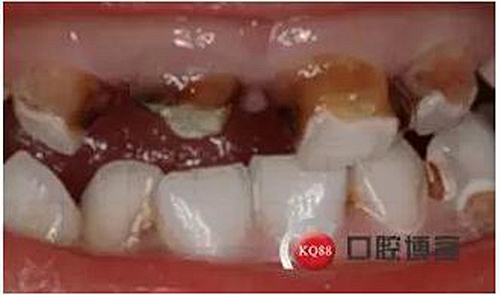

主訴:上前牙齲壞發(fā)黑數(shù)月余

現(xiàn)病史:患兒家長(zhǎng)代述患兒上前牙齲壞發(fā)黑數(shù)月余,速度發(fā)展快,未處置,今來(lái)院就診。

檢查:51,殘冠,牙合面齲壞達(dá)牙本質(zhì)深層,冷熱診無(wú)反應(yīng),探診(-),叩痛(+),唇側(cè)牙齦見瘺管,X線示根尖部見大面積低密度陰影;52,61,62頸部環(huán)狀齲壞達(dá)牙本質(zhì)深層,冷熱診敏感,探診(+),叩痛(-),X線示齲壞低密度陰影與髓腔連通。